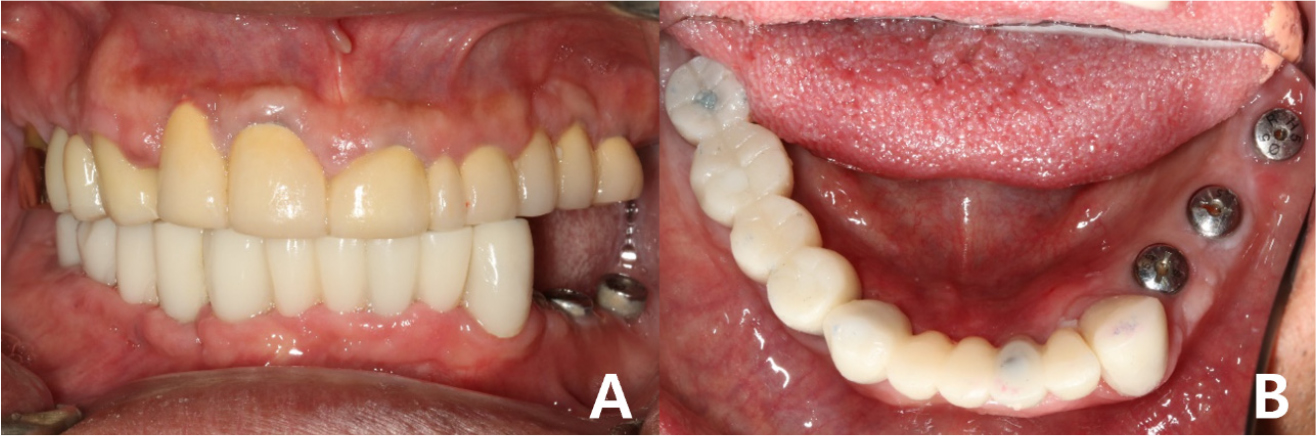

Provisional fixed implant prostheses were placed after the healing period (Fig. 8). The final prostheses were planned to be completed after verifying the vertical dimensions and occlusion using the provisional prostheses.